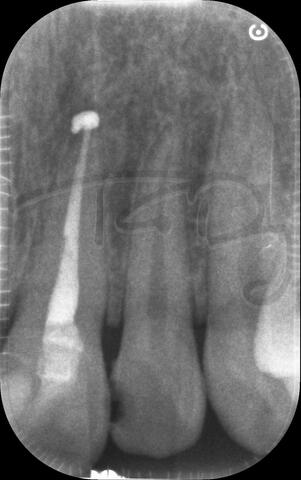

I am pleased to take endodontic referrals. Curved canals >30 degrees and potentially greater than 50 degrees can be negotiated. Sclerosed canals accessed. Post spaces prepared and the patient returned to you ready to restore.In most cases existing crowns, bridges and veneers can be retained with the endodontic access aesthetically restored after the full canal network has been treated.In the first instance I would prefer a radiograph and a brief list of patient expectations and a tooth history.

I really enjoy undertaking root canal treatments - rising to the challenge and helping people out of dental pain for the long term.I was privileged to be asked to speak at the 2016 BDA Conference, where I have a lecture about providing quality endodontic outcomes to patients, working as a generalist. Avoiding problems and pitfalls and maximising efficiency. One of the main matters that he covered was understanding that what is seen on plane radiography is utterly misleading and should not be the criteria by which a generalist continues treatment once it has been started.

At the 2016 BDA Conference, Thomas spoke about providing quality endodontic outcomes to patients, working as a generalist. Avoiding problems and pitfalls and maximising efficiency. One of the main matters that he covered was understanding that what is seen on plane radiography is utterly misleading and should not be the criteria by which a generalist continues treatment once it has been

started.